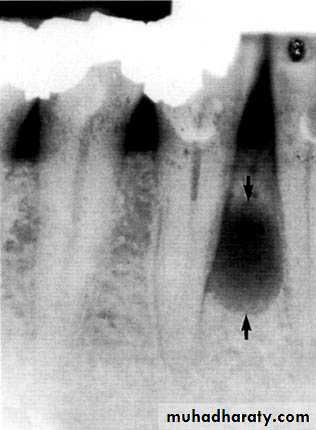

Radiographically :

• Multiple radiolucent areas in the interdental & interradicular bone.

• teeth seem to hang in air. Exfoliation of teeth & teeth germ are common, ulceration of overlaying mucosa.

Loss of the lamina dura and the granular texture of the bone pattern.